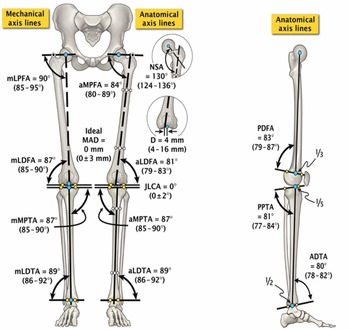

Principles of Deformity Correction: Including the Complete。mqdefault.jpg。Principles of deformity correction | PPT。茨城県産コシヒカリ こだわり新米 5kg 令和6年9月収穫。。。タイトル principles of deformity correction著者 Dror Paley やや経年変化はございますが、書き込みや破れ等はございません。Principles of deformity correction | PPT